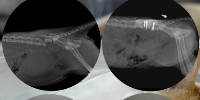

Sou a Karen, criei essa vaquinha para arrecadar um valor para custear as despesas e cirurgias do meu gatinho de estimação. Caio foi mordido por um cachorro, fraturou a vértebra L6 e teve uma eventração no intestino. Graças a Deus conseguimos realizar as cirurgias para corrigir a coluna e eventração. Porém ele ainda está internado e tendo os cuidados finais para voltar pra casa. Conto com a ajuda de vocês. Deus abençoe ❤️